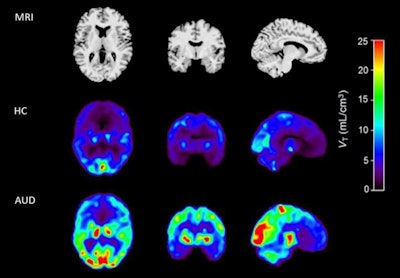

MRI (top panel) and coregistered F-18 AS2471907 PET images of a healthy control (middle panel) and an age- and sex-matched individual with AUD (bottom panel). Image courtesy of Neurobiology of Stress.

According to the findings, PET scans revealed 41.7% higher overall beta-11 HSD1 activity in the prefrontal-limbic circuit in the AUD group compared to the healthy control group, the researchers wrote.

Specifically, mean F-18 AS2471907 radiotracer values were higher in the AUD group by 47% in the amygdala, 36% in the caudate, 52% in the anterior cingulate cortex, 39% in the hippocampus, and 36% in the ventromedial prefrontal cortex (vmPFC).